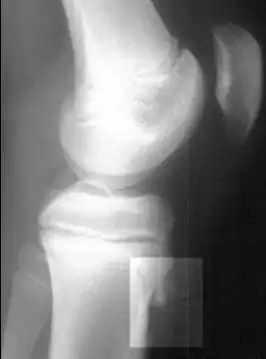

Os fatores de risco incluem o uso excessivo, especialmente esportes que envolvem correr ou pular. O mecanismo subjacente é a tensão repetida na placa de crescimento da tíbia superior. O diagnóstico é tipicamente baseado nos sintomas. Uma radiografia simples pode ser normal ou mostrar fragmentação na área de fixação.[5]

O diagnóstico é feito com base em sinais e sintomas,[9][15] palpação da tuberosidade da tíbia gerando dor,[16] além do exame radiográfico.[17]